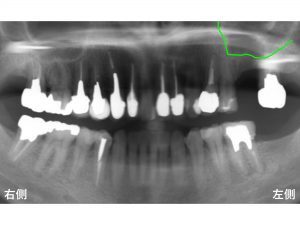

わかりやすいように骨吸収の状態を線でかいて見ます。

そして緑線が上顎洞の一番下の部分です。